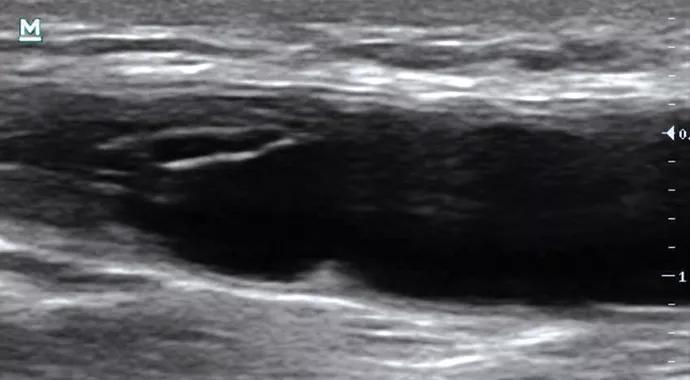

Case Profile 2: Progressive Radial Neuropathy

A 31-year-old woman presented with dorsal left hand and forearm numbness that progressed to wrist and finger drop over several months. Neurological exam revealed sensory loss in the distribution of the left radial nerve and weakness of left wrist/finger extension. EMG showed a left radial neuropathy. Ultrasound (longitudinal view above) revealed a hypoechoic, noncompressible, power-Doppler negative soft tissue mass (arrows) within the antecubital fossa completely surrounding and compressing the radial nerve. The epineurium was intact within the mass. The mass was resected surgically with decompression and internal/external neurolysis of the radial nerve (intraoperative image above). Pathology revealed nodular fasciitis, a benign mesenchymal tumor arising from fascia. The patient’s pain resolved, and weakness was significantly improved at her four-month follow-up appointment.